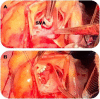

Case presentation: In this case report, we describe a 23-year-old patient with an acute onset of chest pain, shortness of breath, palpitations and dizziness starting 2 days prior to presentation to the emergency department. The patient was initially treated for presumed pulmonary embolism overnight while awaiting CTPA the next morning. However, further examination by the inpatient medical team demonstrated a continuous machinery cardiac murmur. Subsequent echocardiography demonstrated an acutely ruptured SVA with shunting to the right atrium. Emergency surgical repair resulted in an excellent outcome for the patient.